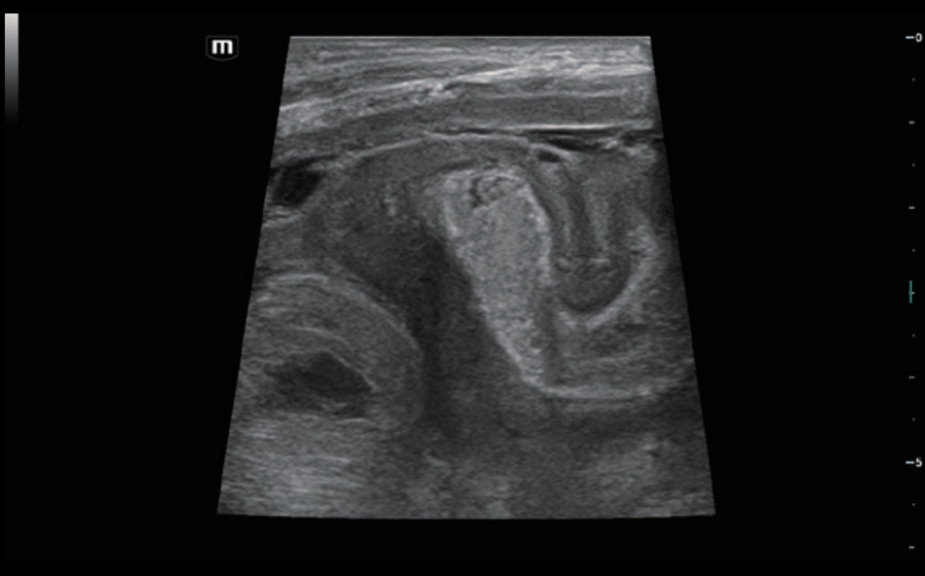

Новейший подход к изучению сосудистой гемодинамики: V Flow

Используются маркированные цветом вектора для индикации значения скорости и направления движения клеток крови. Благодаря сверхвысокой частоте кадров V Flow обеспечивает чрезвычайно четкую, точную и независимую от угла комплексную оценку сосудистой гемодинамики с возможностью всестороннего анализа.

V Flow

Новейший подход к изучению сосудистой гемодинамики: V Flow

Используются маркированные цветом вектора для индикации значения скорости и направления движения клеток крови. Благодаря сверхвысокой частоте кадров V Flow обеспечивает чрезвычайно четкую, точную и независимую от угла комплексную оценку сосудистой гемодинамики с возможностью всестороннего анализа.

V Flow